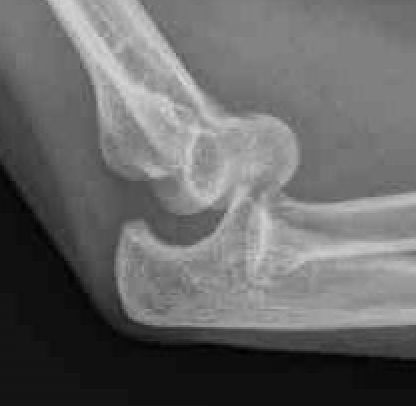

3.  Confirm concentric reduction on xray

Stable Simple Elbow Dislocation

Simple Elbow DislocationElbow Simple Dislocation Reduced

Definition

Elbow fracture with no fractures

Stable in full extension